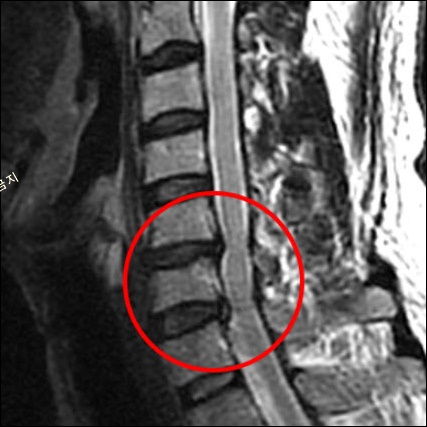

경추(목뼈)는 총 7개의 뼈로 구성되어 있으며, 경추 사이에 충격을 흡수하는 연골 조직인 추간판(디스크)이 있습니다.

추간판이 후방으로 탈출하면 신경을 압박하여 통증을 유발하게 되는데, 이를 보통 '목 디스크'라고 합니다. 목디스크가 발병하면 목이 상당히 불편하면서 어깨가 아프고 팔다리 저림 증상이 나타나게 됩니다.